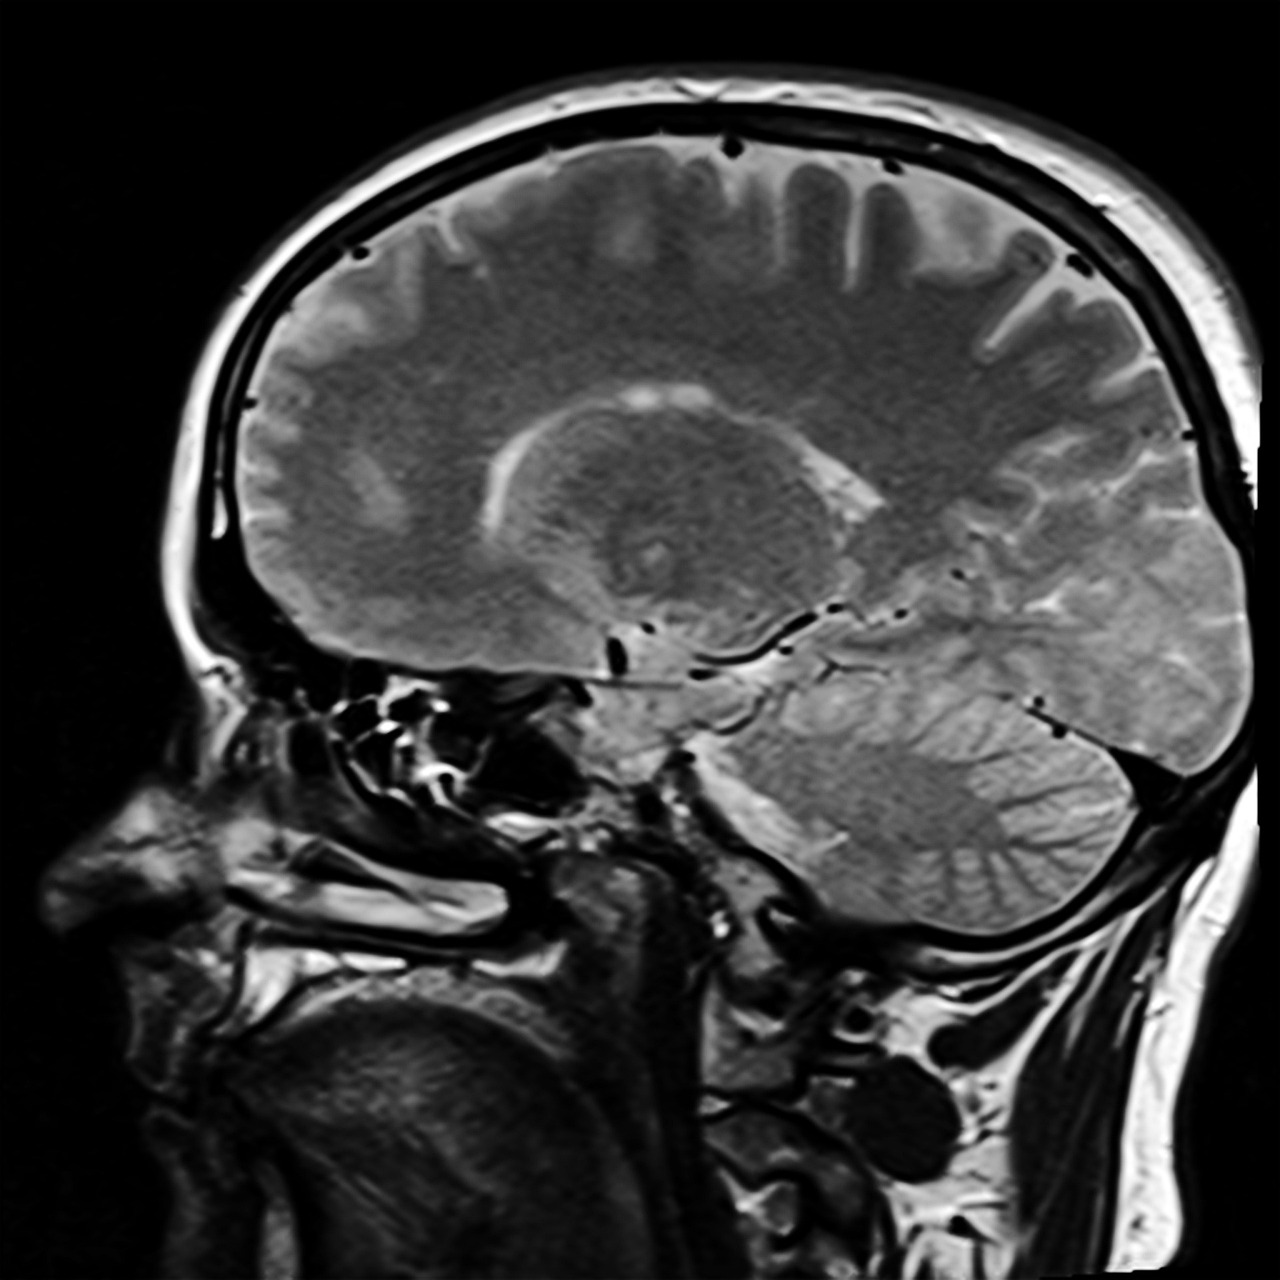

Podczas badania rezonansu magnetycznego cząsteczki wodoru w organizmie reagują na pole magnetyczne, a specjalistyczny aparat rejestruje sygnały wysyłane przez tkanki. Pozwala to na uzyskanie obrazów o wysokiej rozdzielczości, które umożliwiają precyzyjną ocenę zarówno struktur anatomicznych, jak i ewentualnych zmian chorobowych. MRI znajduje szerokie zastosowanie w diagnostyce wielu schorzeń – od chorób ośrodkowego układu nerwowego (mózg, rdzeń kręgowy), przez ocenę narządów wewnętrznych (np. wątroba, nerki), aż po analizę tkanek miękkich i stawów.

Wskazania do wykonania badania rezonansem magnetycznym są bardzo szerokie i obejmują różnorodne dziedziny medycyny. Lekarz może zlecić MRI w przypadku podejrzenia zmian w obrębie ośrodkowego układu nerwowego, takich jak guzy mózgu, stwardnienie rozsiane, udary czy urazy czaszkowo-mózgowe. Rezonans magnetyczny jest także niezastąpiony w diagnostyce schorzeń kręgosłupa oraz rdzenia kręgowego, umożliwiając wykrycie przepuklin dysków, zmian zwyrodnieniowych czy nowotworów. W ortopedii MRI pozwala na ocenę stawów (np. kolanowych, barkowych), więzadeł i ścięgien, co jest szczególnie istotne przy przewlekłych bólach lub po urazach sportowych.

Podanie środka kontrastowego jest szczególnie zalecane w diagnostyce guzów mózgu, przerzutów nowotworowych, chorób demielinizacyjnych (np. stwardnienia rozsianego), ocenie naczyń krwionośnych czy przy podejrzeniu zmian zapalnych w narządach wewnętrznych. Przed przystąpieniem do badania z kontrastem każdy pacjent powinien posiadać aktualny wynik poziomu kreatyniny we krwi – parametr ten ocenia wydolność nerek i pozwala wykluczyć ryzyko powikłań związanych z eliminacją środka kontrastowego z organizmu. Wynik kreatyniny nie powinien być starszy niż 30 dni, natomiast u osób z przewlekłą chorobą nerek wymagane są częstsze kontrole (najlepiej do 7 dni przed badaniem).